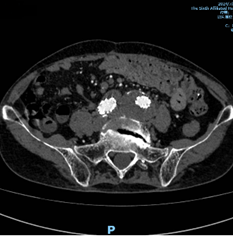

术后半年复查CT显示腹主动脉-双侧髂动脉瘤完全隔绝,右侧髂内动脉血流通畅。